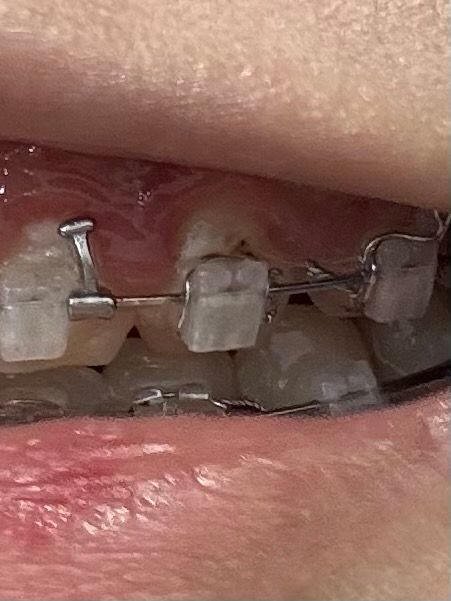

교정 3년차 입니다 이전 질문으로 이게 충치인지 아닌지 사진과 함께 질문을 했었는데 양치하니까 그 부위가 시려서요…

육안으로 보일 정도면 심한 건가요?

이 사진으로 보니 충치가 맞을 것 같네요

교정중에는 치료를 할수가 없습니다. 아마 저부위는 교정장치를 제거하고 확인해봐야 알겟지만 레진 주변으로 착색이 됫을 가능성이 충치보다 더 높습니다.

해당 부분이 착색인지, 충치인지에 대한 감별이 필요합니다. 교정용 브라켓 및 와이어를 착용하고 있다면 음식물이 많이 저류하여 충치 및 치아 착색이 일반적인 경우보다는 잘 일어납니다. 다만 충치라면 해당 교정용 브라켓 및 와이어를 제거하고 다시 교정용 브라켓과 와이어를 붙여야 합니다.